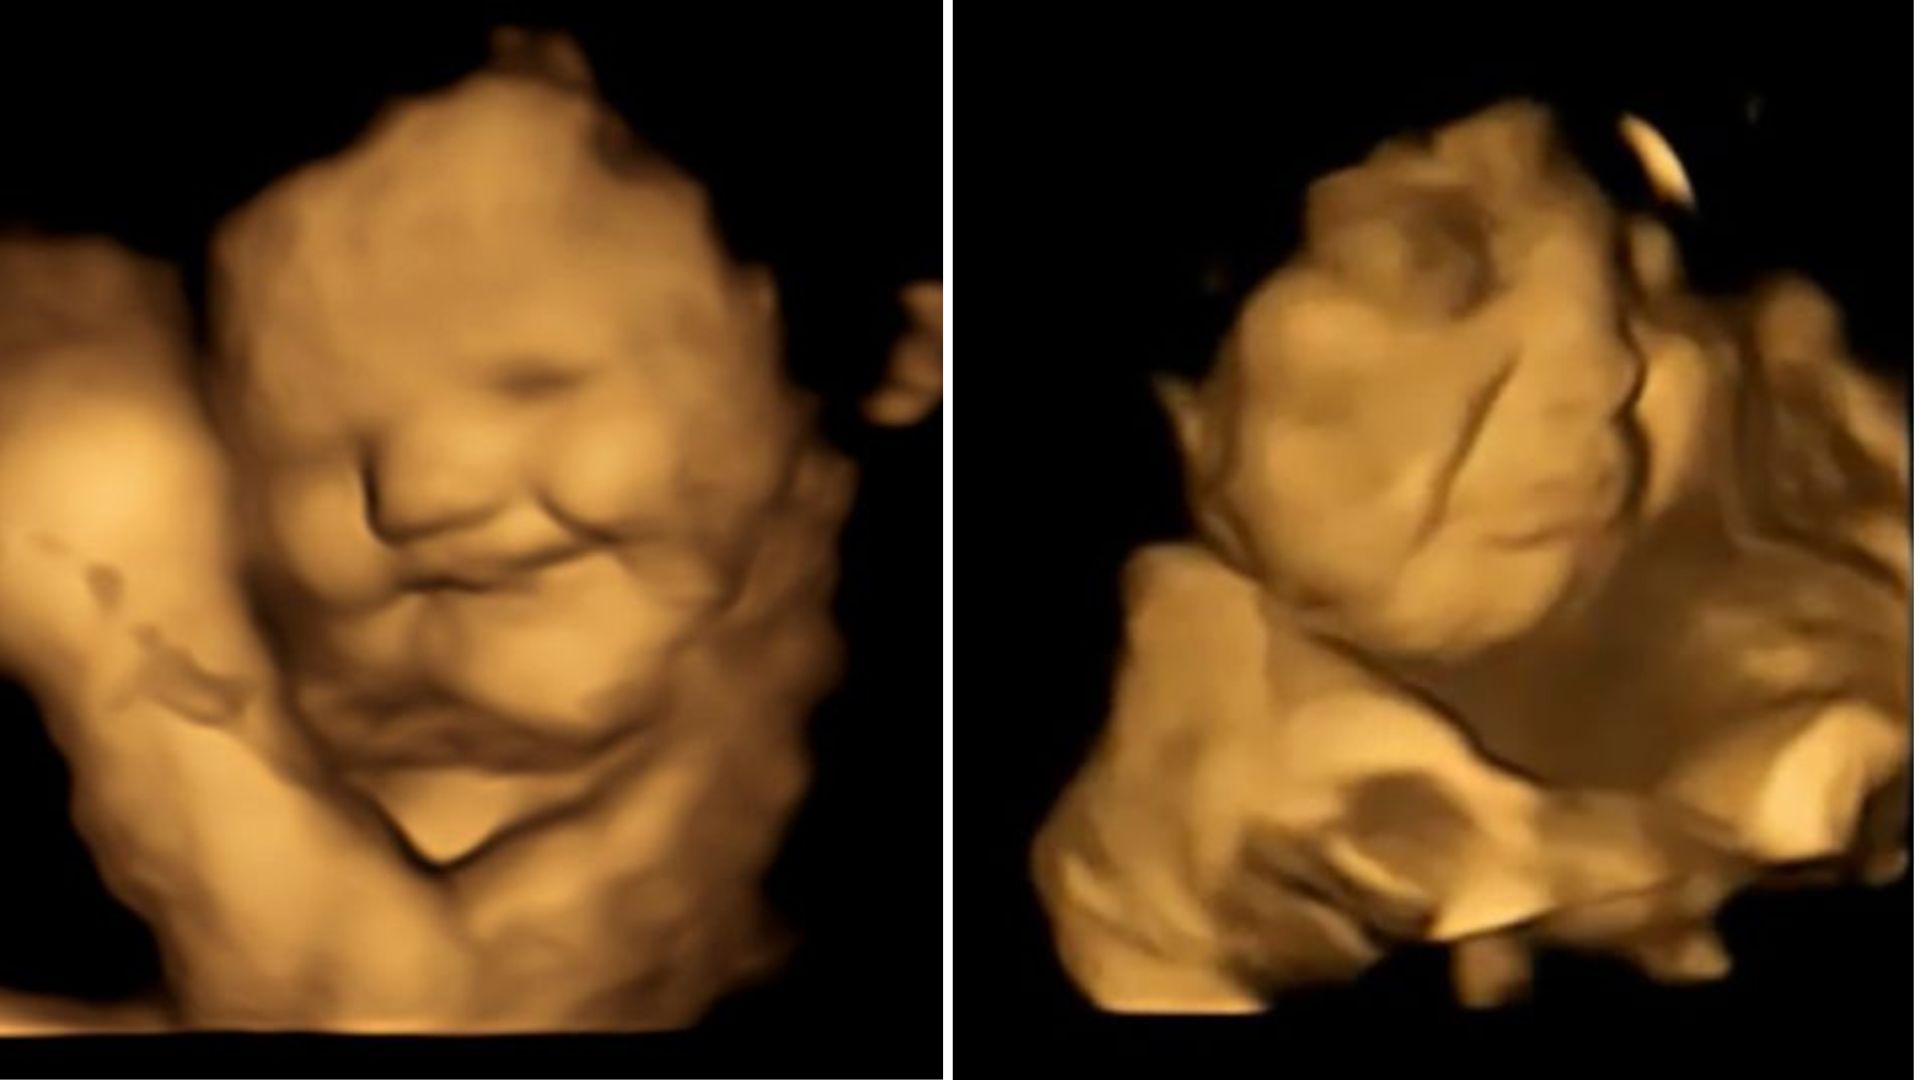

Twenty minutes after consumption, the research team completed 4D ultrasound scans to view fetal facial expressions. The fetuses exposed to carrot showed showed “laughter-face” responses, while the kale-exposed fetuses showed a higher prevalence of “cry-face” responses.

A 4D ultrasound scan of one fetus exposed to carrot. FM6 indicates a “cheek raiser,” while FM12 indicates a “lip-corner puller.” Researchers at Durham University in Northeast England

A 4D ultrasound scan of one fetus exposed to kale. The FM11 indicates a “nasolabial furrow,” while FM16 indicates a “lower-lip depressor.” Researchers at Durham University in Northeast England